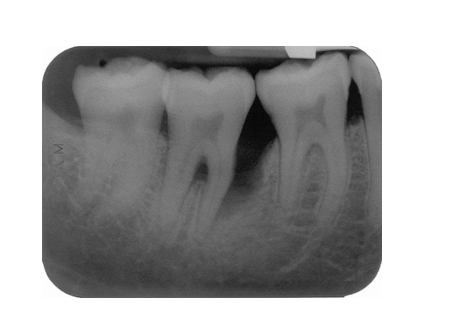

Describe 2 patterns of bone loss evident in this radiograph?

A

• Horizontal and vertical

What explains the development of bone loss on the mesial aspect of the lower right second premolar?

• Presence of plaque accumulation (scalloping) in the distal aspect of the tooth , the canal curvature may have acted as a plaque trap

Following hygiene phase therapy this patient’s oral hygiene was excellent but pockets of >6mm persisted in the lower right quadrant. Open flap debridement was performed

What feature of this patient’s disease which is on the radiograph is most likely to limit the success of this treatment and why?

Fucration involvement due to bone loss making access for cleaning difficult leading to poor prognosis of tooth